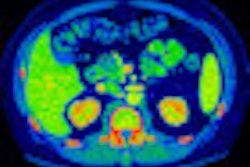

In other news, the company is showing body perfusion CT and dual-energy scanning as works-in-progress. Body perfusion CT can reduce motion artifacts by registering multiple volumes to an original volume, while Toshiba's application of dual-energy imaging uses kVp and mA switching techniques.